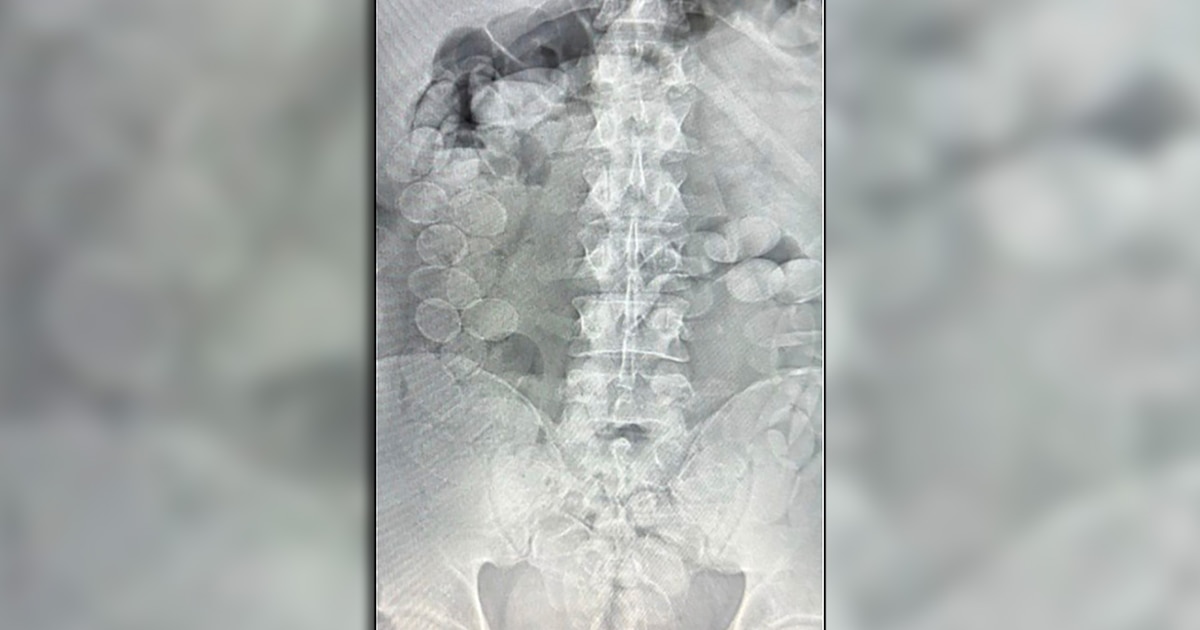

Según reportó el MPF, ambos acusados manifestaron malestar físico y admitieron que habían ingerido cápsulas con estupefacientes. En consecuencia, fueron trasladados al Hospital de Ceres, donde estudios radiográficos confirmaron la presencia de cuerpos extraños compatibles con cápsulas.

Finalmente, expulsaron un total de 185 envoltorios con cocaína : 93 de Sirilo Quispe Carmona (27 años) y 92 de Abel Rocha Risco (28 años), con un peso total de 2.451,3 gramos y una pureza promedio del 85,17%.